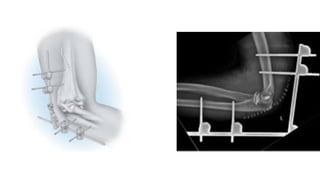

EXTENAL FIXATION

• STATIC EXTERNAL FIXATOR

• HINGE EXTERNAL FIXATOR

• A hinged fixator will allow for range of mo)on exercises to be performed while the external

fixator is in place.

• The key to all hinged devices is an understanding of the axis of elbow rota)on.

• If the axis pin is malaligned, maltracking or even disloca)on of the elbow may occur during

mo)on.

• Elbow mo)on is ini)ated postopera)vely within the first week.

• The frame is leJ in place for approximately 4 to 6 weeks, depending on a number of factors

including the stability of the elbow, associated pin tract problems.

STATIC EXTERNAL FIXATOR

• The elbow is placed at 90 degrees of flexion with the joint concentrically reduced.

• Two pins are placed in the humeral shaJ laterally and two pins are placed in the ulnar shaJ

laterally in a posi)on that allows for forearm rota)on.

• Open pin placement is recommended to avoid injury to the radial nerve.

• A sta)c frame is assembled with the elbow joint reduced.

• The external fixator is leJ in place for approximately 4 weeks.